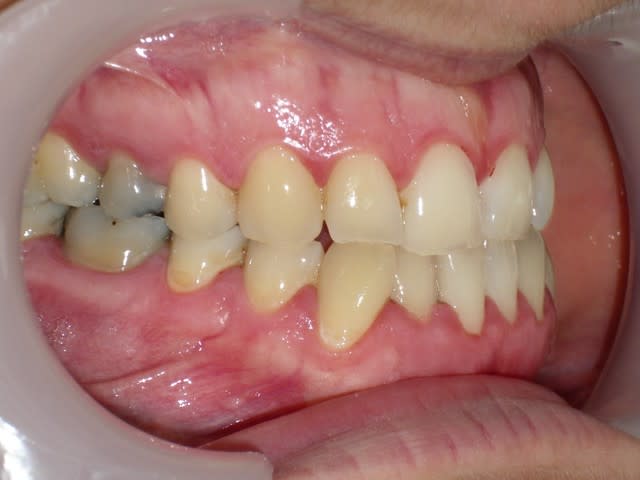

voici de la cas d'un jeune dame de 23 ans qui présente une full classe III subdivision Droite (associée à des compensations incisives de classe III), sur un terrain hyperdivergent. on note un encombrement inferieur d'environ 2 mm et une abrasion des bords triturants des incisives inf (Motif de la consultation)